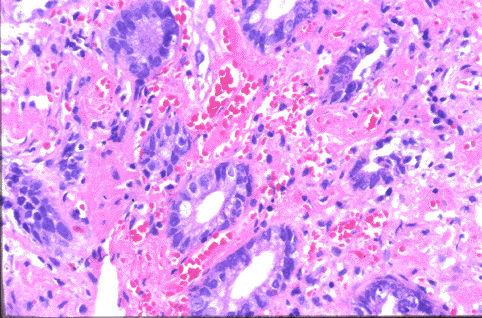

易与肿瘤混淆的炎症性及非肿瘤性疾患、病变

肠(大肠、小肠)的炎症性疾患、病变

病原性大肠炎

图像上需要与恶性淋巴瘤进行鉴别的一例O157大肠疾患 (福冈市南区 高宫外科)

病理切片(微观)